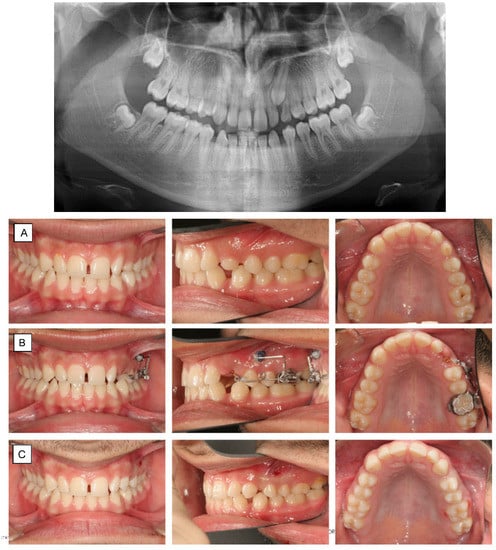

10. Molar Uprighting

11. Dental Transposition